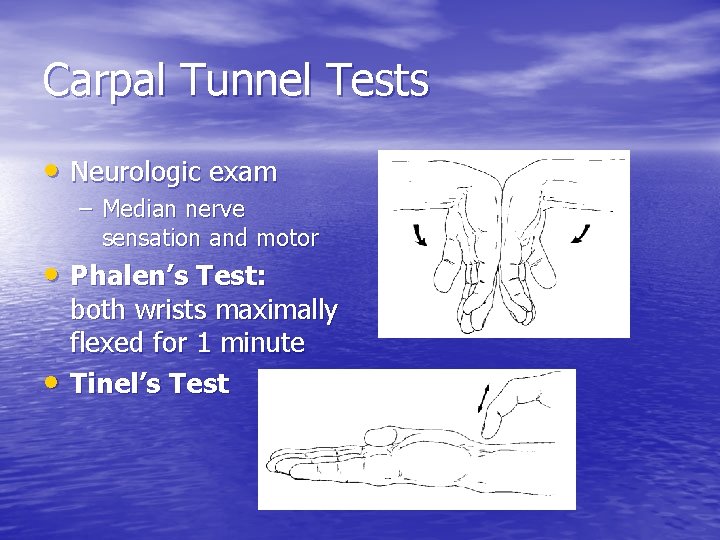

Carpal Tunnel Tests • Neurologic exam – Median nerve sensation and motor • Phalen’s Test: • both wrists maximally flexed for 1 minute Tinel’s Test